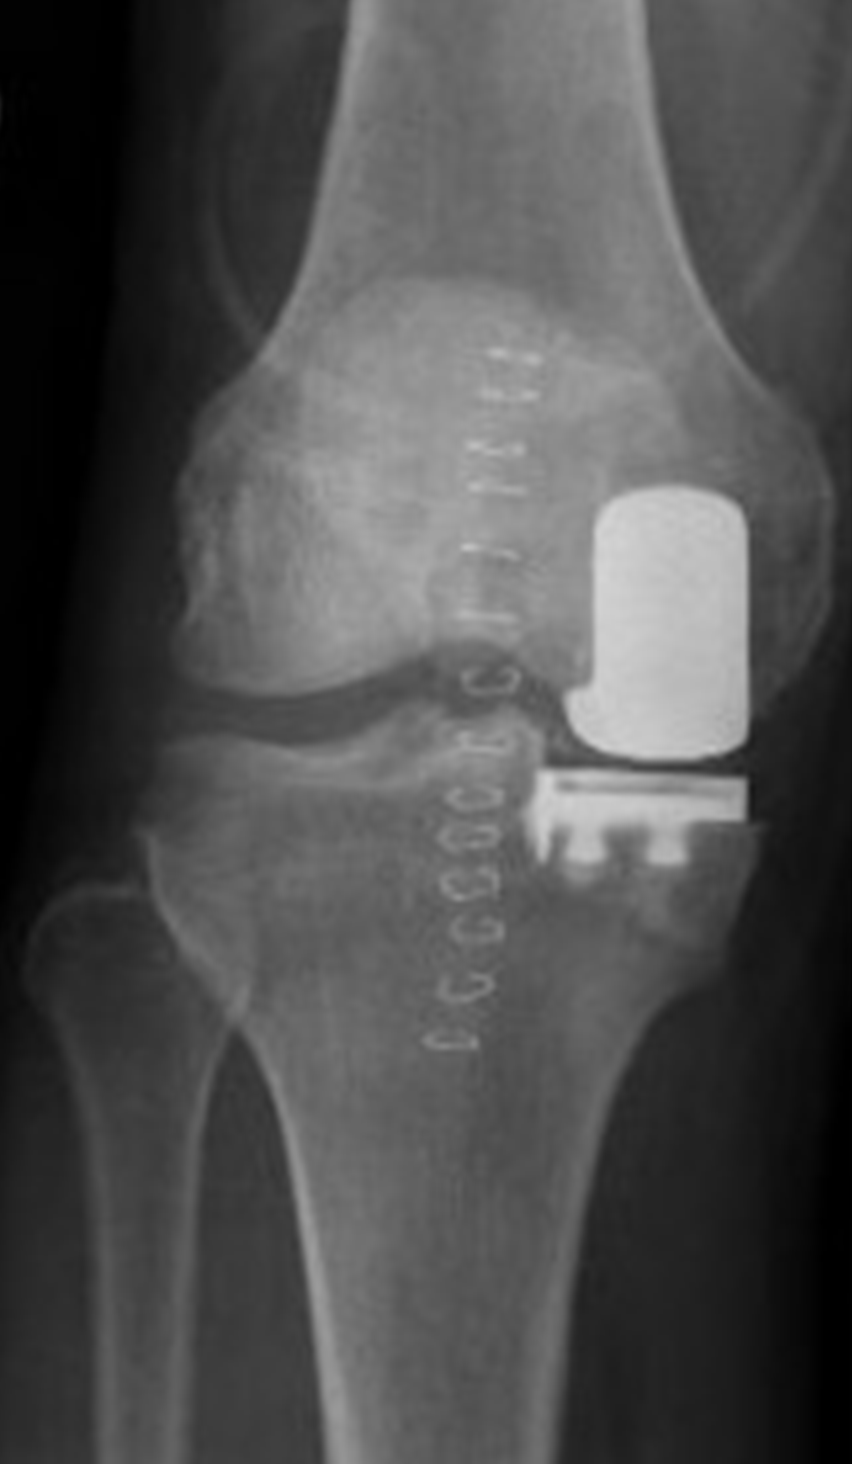

From www.sciencephoto.com

Partial knee replacement, Xray Stock Image C048/6921 Science Should I Have A Partial Knee Replacement partial knee replacement may help relieve osteoarthritis if it is only present in part of the knee. why you might say now’s the time here are seven signs that the time might be right for a knee replacement:. if you have osteoarthritis in only one part of the knee, a partial knee replacement is considered the better. Should I Have A Partial Knee Replacement.